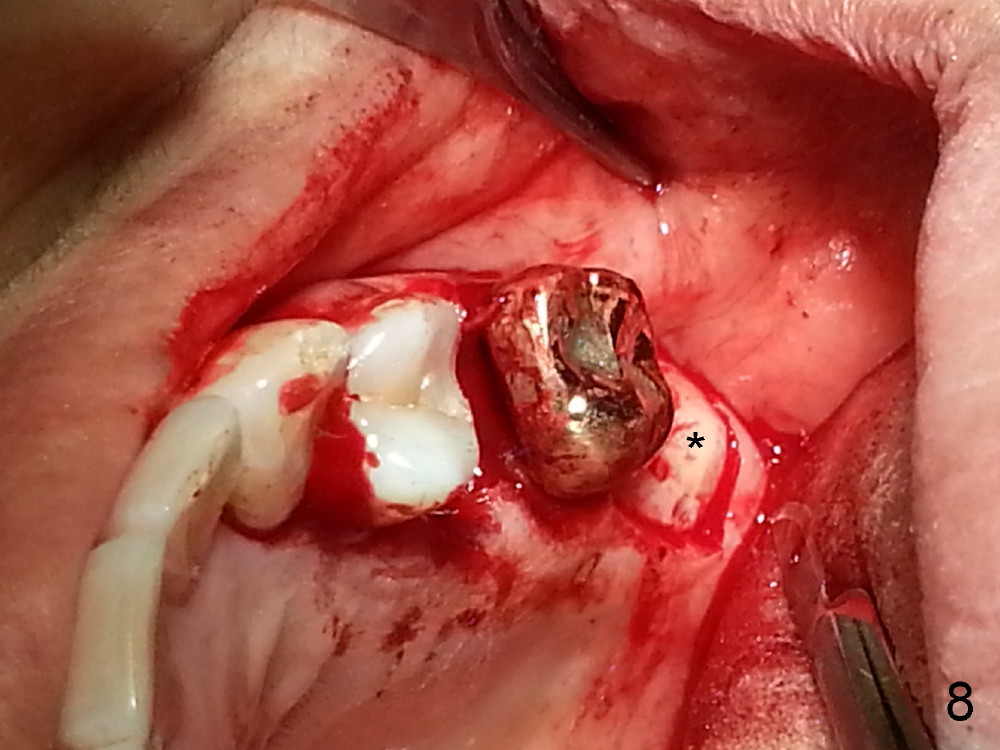

The tooth #13 appears to be affected by periodontits and occlusal trauma (Fig.1*). After using a periotome (Fig.2), the tooth is extracted (Fig.3). The buccal flap is raised (Fig.4). Gingival graft is to be harvested from the site of #15 (Fig.5). The tissue is elevated buccally (Fig.6) and separated (Fig.7). The donor site is covered by a collagen membrane (Fig.8*). A diamond bur is used to induce bleeding from the socket (Fig.9*). Osteotomy is initiated (Fig.10) and enlarged (Fig.11,12). A tapered implant is being placed (Fig.13-15) following internal sinus lift (Fig.16,17). The implant is placed subcrestally, followed by bone graft (Fig.18), soft tissue graft (Fig.19), and suturing (Fig.20 <, Fig.21).